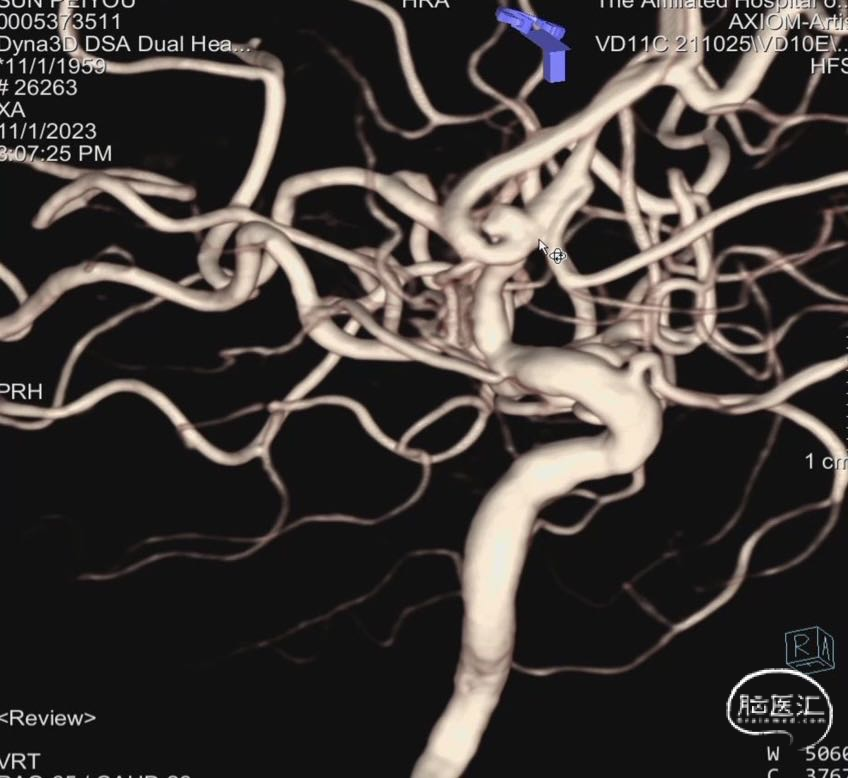

术前DSA三维重建。

左侧大脑前动脉A2段宽颈动脉瘤。